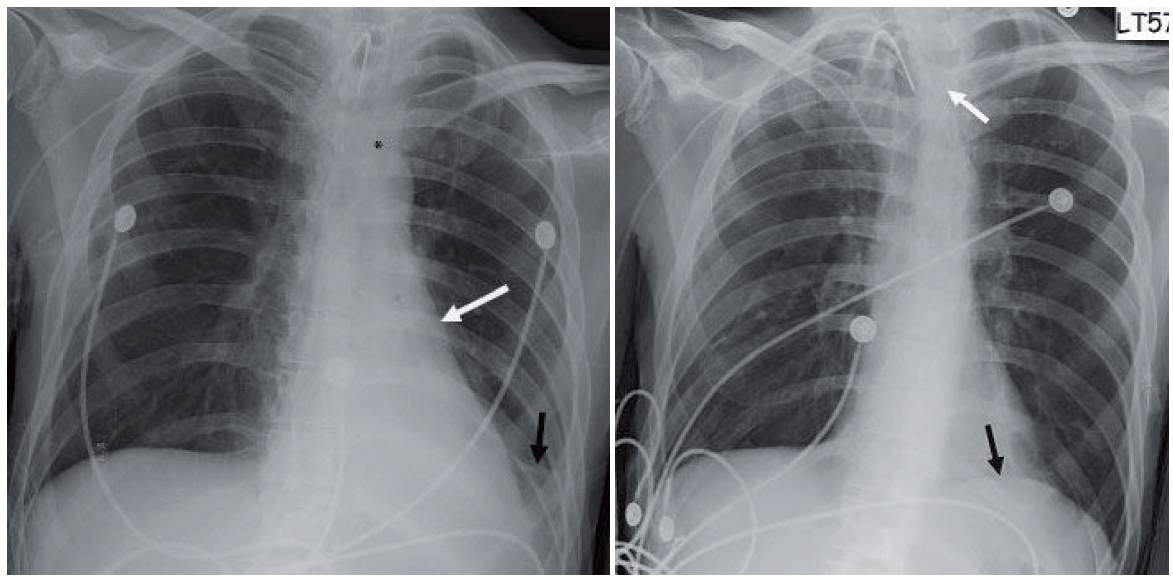

- Follow-up chest radiograph obtained the following day shows near-complete resolution. The left hemidiaphragm can now be seen (black arrow in second image) and the left heart border has regained the normal curvature. The peripherally inserted catheter flipped into the left brachiocephalic vein (white arrow).